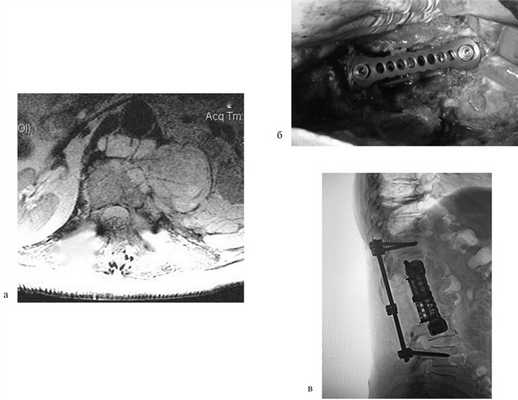

Пример торакоскопической операции на грудном отделе позвоночника при опухоли (ганглионевроме)

Клинический пример

Пациентка Н., 69 лет, поступила в апреле 2016 г. в отделение онкоортопедии МНИОИ им. П.А. Герцена с диагнозом хондросаркома позвонка LII T3N0M0 G1 III стадии. Пациентка самостоятельно не передвигалась из-за выраженного болевого синдрома в проекции поясничного отдела позвоночника. 3 балла по ECOG, 50 баллов по шкале Карновского и 3 балла по Watkins. Парапарез нижних конечностей до 2 баллов. В апреле 2016 г. 1-м этапом выполнена декомпрессивная ламинэктомия позвонков LI—II с задней стабилизацией на уровне позвонков ThXII—LIII. Послеоперационный период без осложнений. Далее в мае того же года выполнен 2-й этап хирургического лечения: корпорэктомия позвонков LI—II с эндопротезированием тел позвонков телескопическим эндопротезом (рис. 3). Пациентка выписана на 9-е сутки после операции, передвигалась самостоятельно без дополнительных средств опоры (1 балл по ECOG, 80 баллов по шкале Карновского, 1 балл по шкале Watkins), рекомендован динамический контроль онколога по месту жительства.

Рис. 3. МРТ-картина до хирургического лечения (а). Тело позвонка LII с признаками деструкции, структура его представлена опухолевой массой размером 87×57×67 мм. Интраоперационная фотография (б), боковой доступ. Установленный телескопический эндопротез тел позвонков LI—II c боковой фиксирующей пластиной. Послеоперационная рентгенограмма поясничного отдела позвоночника (в). Металлоконструкция установлена корректно. Исследование выполнено на 1-е сутки после хирургического лечения.